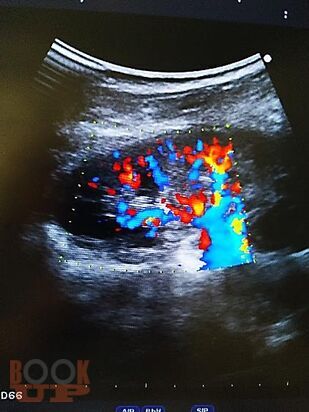

Пособие содержит материал, отражающий современные данные о лечебно-диагностических концепциях основных врождённых и приобретённых урологических заболеваниях взрослых и детей. В пособии раскрыты ключевые позиции, этиологии, патогенеза, классификации, клинических проявлений, диагностики, консервативного и хирургического лечения, возможных осложнений и исходов урологических заболеваний. Сделан акцент на эмбриопатогенез и пренатальную диагностику врождённых аномалий развития органов мочевыводящей системы у детей. Пособие содержит перечень вопросов для самоконтроля, тестовые задания и ситуационные задачи.